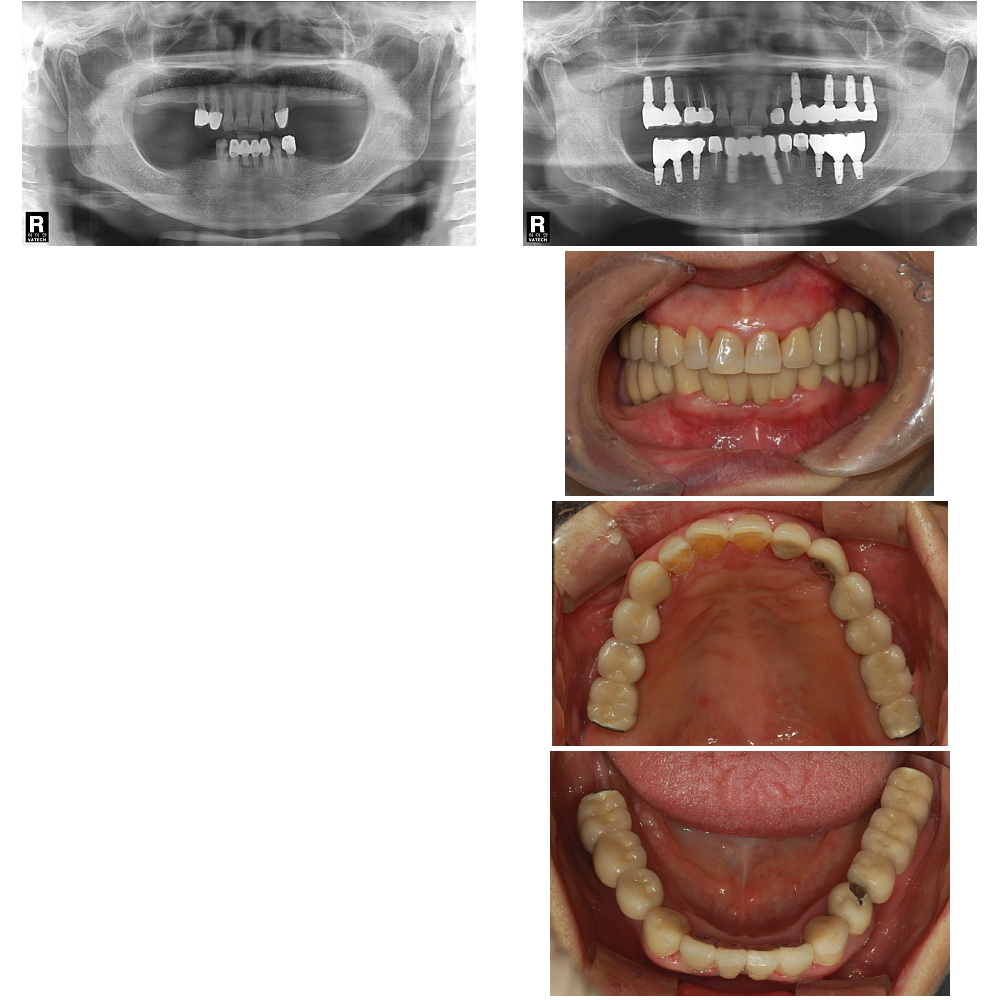

| ÀÓÇöõÆ® ¿©·¯°³, ... |

| »ó¾Çµ¿ À̽ļú°ú ÀÓ... |

| ÀÓÇöõÆ®´Â ÀÚ½ÅÀÇ »À¿¡ Àΰø Ä¡¾Æ¸¦ ¸¸µé°Ô µÇ´Â °ÍÀ̹ǷΠÀûÀýÇÑ ¾çÀÇ »À°¡ ÀÖ¾î¾ß¸¸ °¡´ÉÇÕ´Ï´Ù. »À°¡ ºÎÁ·ÇÒ °æ¿ì Àΰø»À¸¦ ÀÌ¿ëÇÏ¿© »À¸¦ º¸°ÇÏ´Â ¼ú½ÄÀÌ Ãß°¡ÀûÀ¸·Î ÇÊ¿äÇÒ ¼ö ÀÖ½À´Ï´Ù. ¿©·¯ °¡Áö ¹æ»ç¼± »çÁø ¹× Áø´Ü¸ðµ¨À» ÅëÇØ¼ »À¿¡ ´ëÇØ Æò°¡Çϰí ÀÓÇöõÆ® °èȹÀ» ¼¼¿ì°Ô µË´Ï´Ù. |

| Àΰø »Ñ¸®¸¦ ½É´Â ¼ö¼úÀÔ´Ï´Ù. »À¿¡ Àû´ç·®ÀÇ ±¸¸ÛÀ» ¶Õ°í Àΰø »Ñ¸®¸¦ ½É¾îµÎ°Ô µË´Ï´Ù. Ä¡¾Æ ÁÖÀ§¿¡ ¿°ÁõÀÌ ½ÉÇÏÁö ¾ÊÀ¸¸é Ä¡¾Æ¸¦ »Ì°í ´çÀÏ¿¡ ¹Ù·Î ÀÓÇöõÆ®¸¦ ½Ä¸³ÇÏ´Â °æ¿ìµµ ÀÖ½À´Ï´Ù. ÀÌÈÄ ¾Æ·¡ Åο¡¼´Â 2-3°³¿ù, ÀÅο¡¼´Â 4-6°³¿ùÀÇ Ä¡À¯±â°£ÀÌ ÇÊ¿äÇÏ¸ç »ÀÀ̽ÄÀ» Çß´Ù¸é Á» ´õ ¿À·£ ±â°£µ¿¾È ±â´Ù·Á¾ß ÇÏ´Â °æ¿ìµµ ÀÖ½À´Ï´Ù. ÀϹÝÀûÀ¸·Î ÀÌ ±â°£ Áß¿¡´Â ÀÓÇöõÆ®°¡ ÈûÀ» ¹ÞÀ¸¸é Ä¡À¯¿¡ ¹æÇذ¡ µÇ±â ¶§¹®¿¡ º¸Ã¶¹°À» Á¦ÀÛÇÏÁö ¾ÊÀº »óÅ¿¡¼ Ä¡À¯¸¦ ½ÃŰÁö¸¸ ¾Õ´Ï¿Í °°ÀÌ ½É¹ÌÀûÀÎ ¹®Á¦°¡ Àְųª ¶Ç´Â ¿©·¯ °³ÀÇ ÀÓÇöõÆ®¸¦ ÀÌ¿ëÇÏ°Ô µÇ´Â °æ¿ì ¹Ù·Î º¸Ã¶¹°À» Á¦ÀÛÇÒ ¼ö ÀÖ´Â °æ¿ìµéµµ ÀÖ½À´Ï´Ù. |